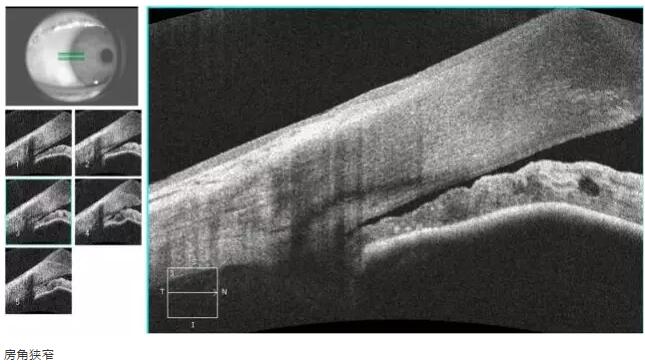

1:OCT 前节断层扫描可识别出巩膜突、Schwalbe 线 、Schlemm 管 等结构,且辨识度很高,巩膜突(78.9%)、Schwalbe线(93.3%),若对图像进行放大查看, 更佳。